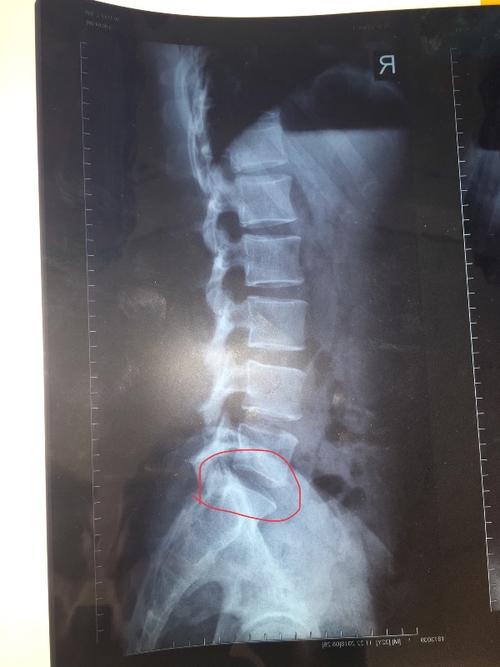

哪位懂骨骼,帮看看我腰椎有没有问题呗?